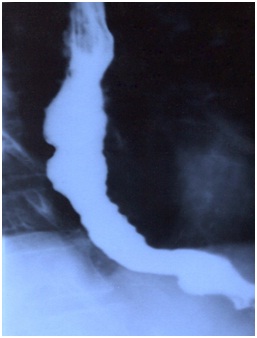

After the Treatment

Oesophageus opened out completely with the treatment.

After about 2 months of regular treatment, she had started eating and drinking freely without any discomfort and had gained another 4 kilograms; her weight was only slightly lesser than normal now. Her treatment was continued for a few more months since this was a case with pathological changes in the body and it takes time for the pathology to be reversed. The patient continued to improve on the treatment and was very satisfied with the results.

Conclusion: It is possible to treat Oesophageal Stricture with right homeopathic medicine. Total Beak like stricture responded to the treatment to normal intake itself is a good result.